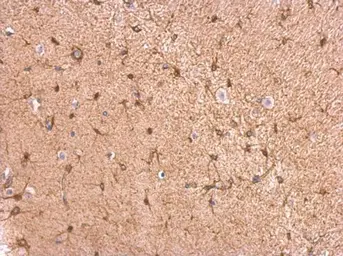

GPBB antibody detects GPBB protein at cytosol on mouse fore brain by immunohistochemical analysis.

Sample: Paraffin-embedded mouse fore brain.

GPBB antibody (GTX104291) dilution: 1:500.

Antigen Retrieval: Trilogy™ (EDTA based, pH 8.0) buffer, 15min